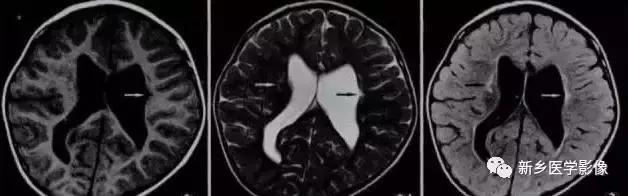

8.胼胝体发育不良

在脑发育腹侧诱导晚期,新形成的端脑嘴侧壁的背侧部分增厚、内陷,向后沿尚未完全发育的大脑半球间裂延伸。两个月后形成一个连合即胼胝体纤维的细胞框架,该细胞框架形成后胼胝体相应部分立即发育。膝部先发育。然后是体部、压部.位于胼胝体膝部后下方的胼胝体嘴最后发育。如果胼胝体发育过程中出现有害因素,就有可能导致胼胝体发育不良.表现为完全缺如或部分缺失。常表现为膝部存在或膝部和体部存在。压部和胼胝体嘴缺失。

胼胝体发育不良可见单独发病,但更常见的是伴有中枢伸经系统的其他畸形,包括胼胝体周围脂肪瘤、脑膨出、交通性脑积水Chaiarii畸形、Dandy-Walker囊肿、脑裂畸形等。临床上可无症状或仅有轻度临床症状,临床检查可见眼距过宽、大头畸形、智力发育迟滞等。胼胝体缺失时,MR冠状位上侧脑室前角呈新月形表现,侧脑室体部分离,呈垂直状平行走行。